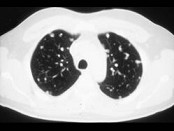

- 单项选择题.女,72岁, 咳嗽,胸闷, 呼吸困难1月余,1年前行结肠癌根治术, CT检查如图,请选择最可能的诊断 ( )

B、肺转移瘤